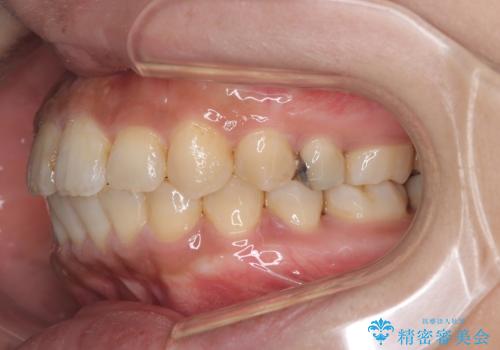

- 主訴:学生時代に矯正治療したが、後戻りしてしまった。上下前がのガタつきを治したい。

食品関係に努めており、頻繁に物を口にするためマウスピース矯正は装着時間を守ることが難しいことから非抜歯のワイヤー装置にて治療することとなりました。

ワイヤー矯正(審美装置)非抜歯 治療期間:1年8か月

一日に物を口にする回数が多い方はマウスピース矯正における推奨装着時間を守ることや、その都度歯磨きをすることが難しいため、ワイヤー矯正での治療となりました。

途中、大臼歯の遠心移動のためリンガルアーチを使用しています。